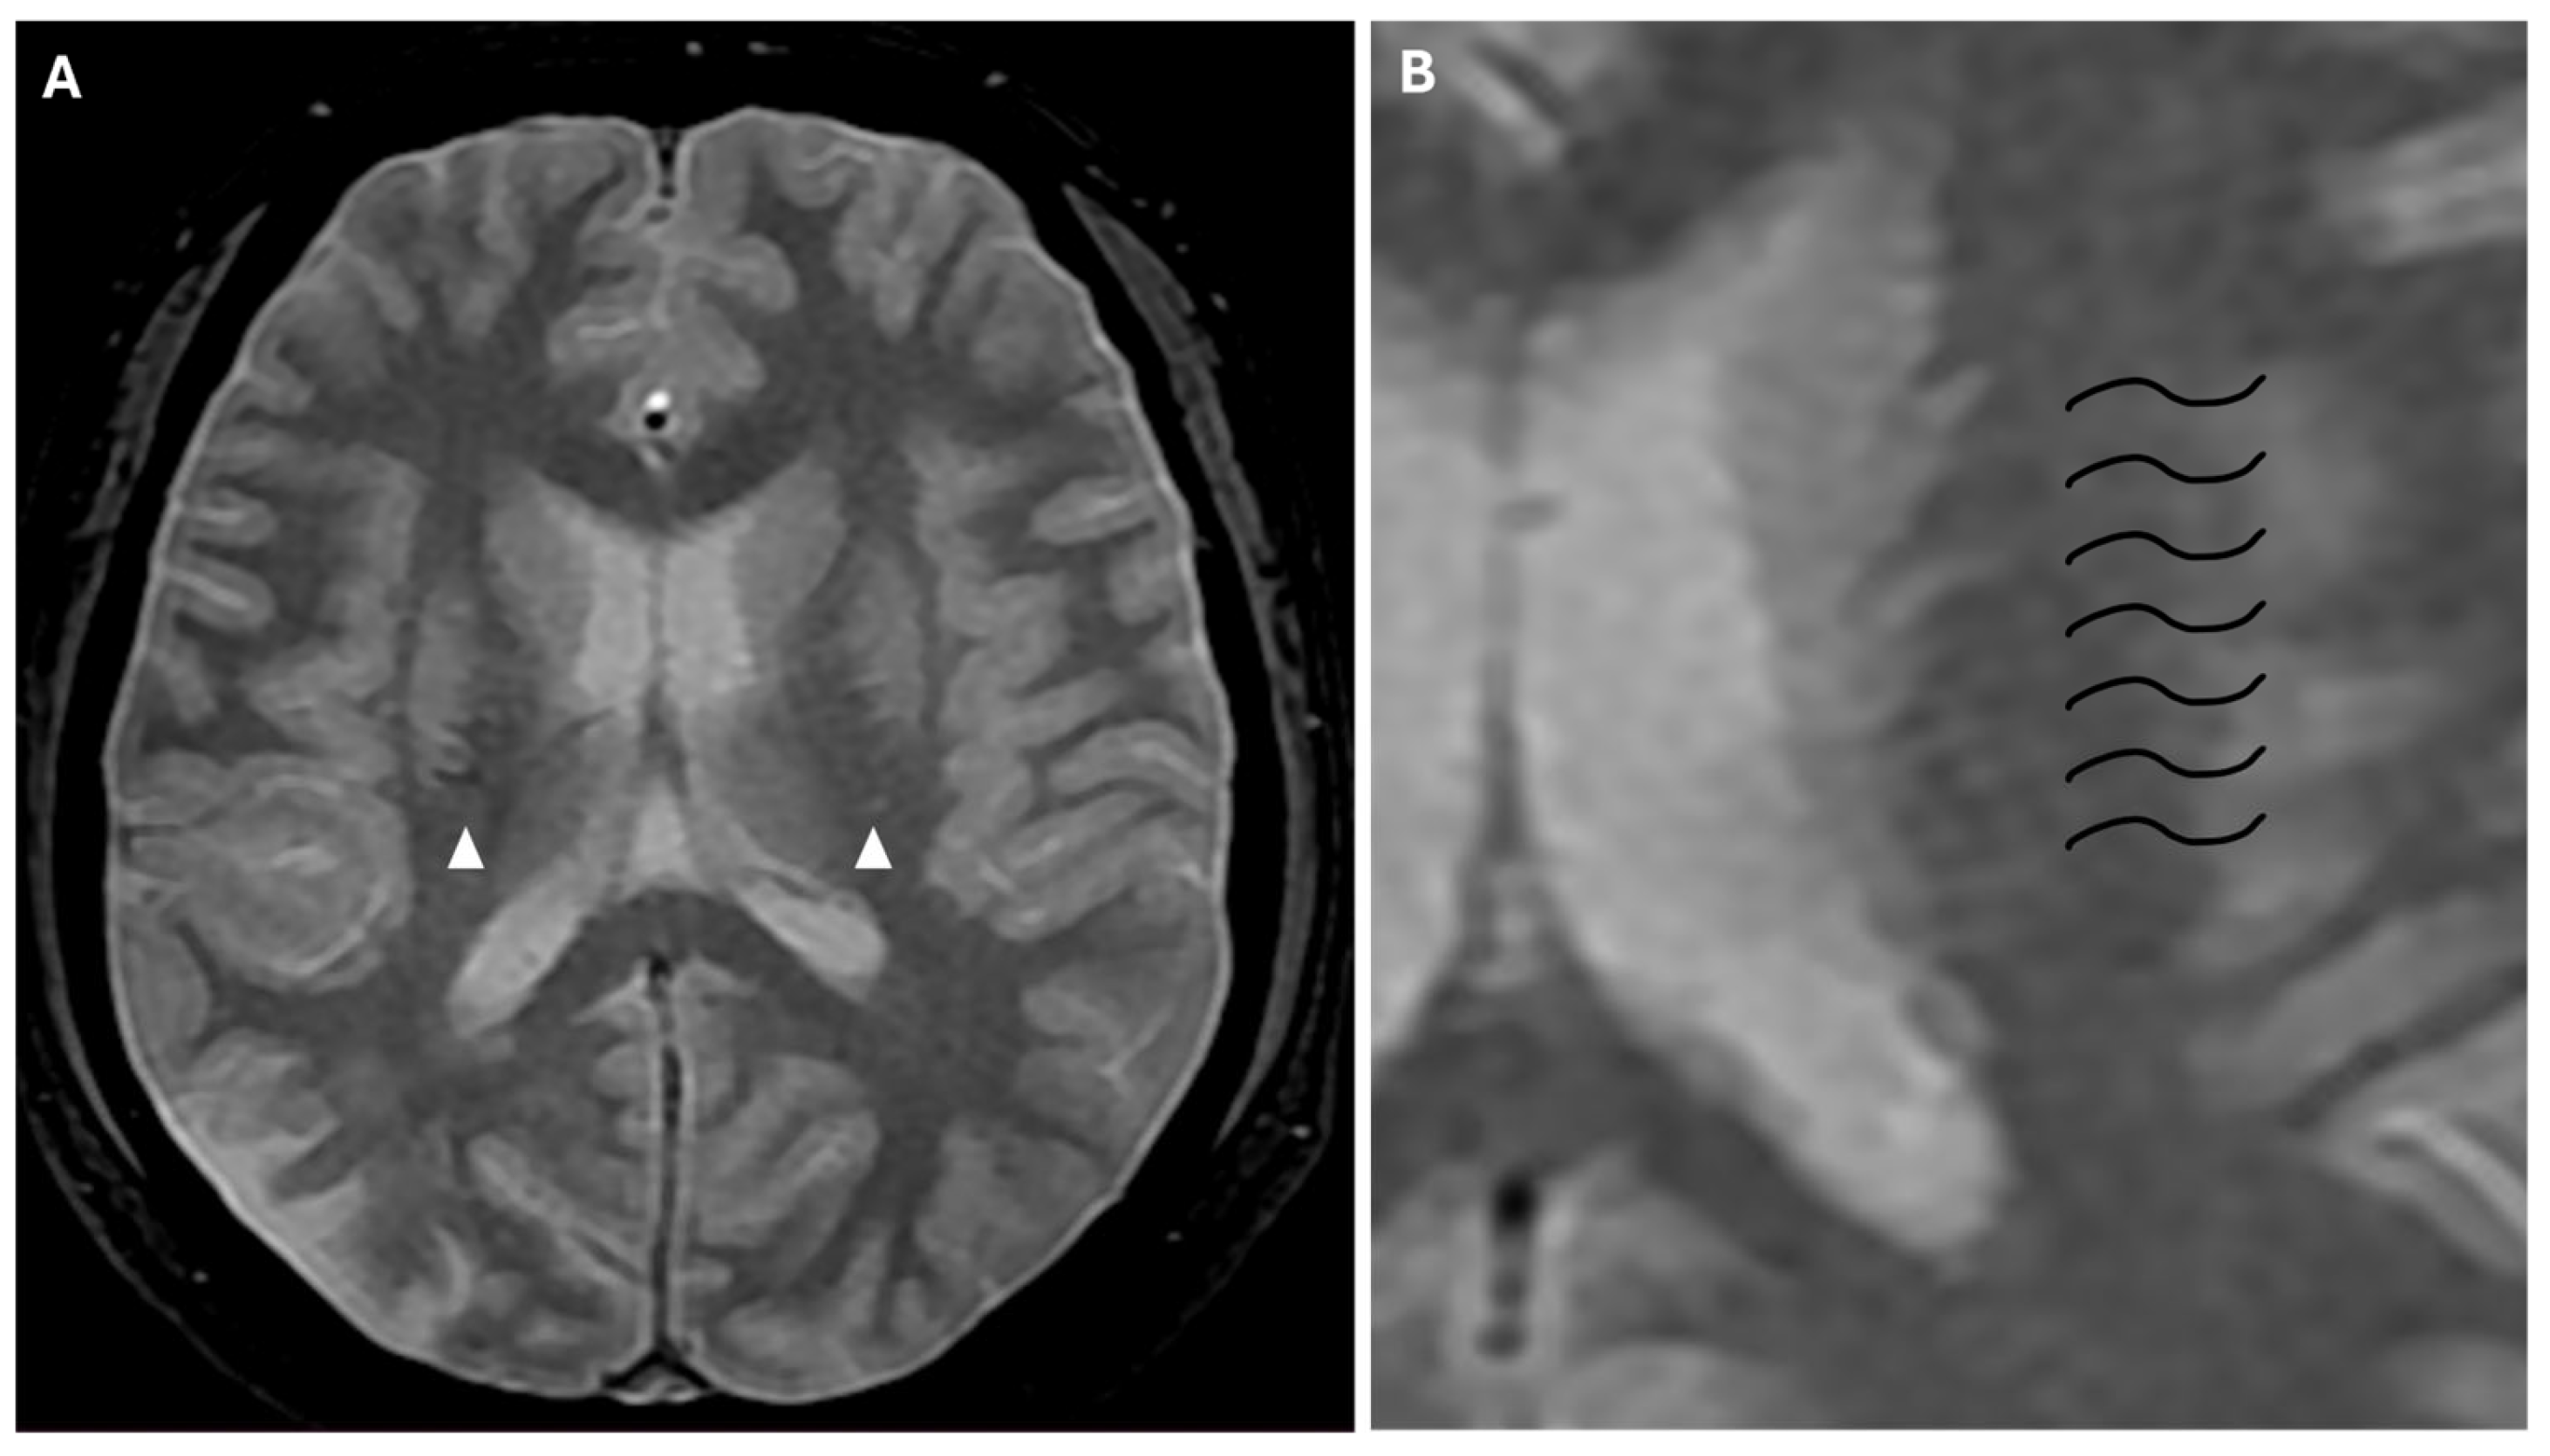

Another phenomenon that can be observed on FLAIR sequences is the “medullary streak” sign, which is characterized by a hyperintense streak oriented perpendicularly to the lateral ventricle (“periventricular medullary veins/FLAIR hyperintense streaks”); despite its etiology remaining ambiguous, the condition has been associated with ischemia and could represent collateral vasculature, stagnated cerebrospinal fluid, or vasogenic edema (Figure 7).

Figure 7. Axial (A) and coronal (B) 3d FLAIR sequences show a hyperintense streak area oriented perpendicularly to the right lateral ventricle (white arrows), representing the “medullary streak” sign. Note the right parietal subacute ischemic lesion (white arrowhead).

Approximately half of adult patients with MMD may develop intracranial hemorrhage. The location of the hemorrhage can be subarachnoid, intraventricular, or intraparenchymal, more often within the basal ganglia [3]. Microbleeds can be detected through the use of gradient echo T2* sequences or susceptibility-weighted imaging (SWI), the latter being a 3D gradient-echo sequence with an increased spatial resolution and higher sensitivity to these alterations. Microbleeds may be associated with leakage from dilated and fragile collateral vessels, such as the anterior choroidal or posterior communicating arteries. These alterations also have a prognostic value, as they indicate an increased risk for intraventricular hemorrhage, particularly if located in the periventricular area [2]. In fact, rupture of prominent and fragile anterior choroidal arteries leads to intraventricular hemorrhage, as often observed in MMD [22]. Furthermore, SWI and FFE sequences can detect prominent medullary veins, identifying hypointense blooming artifacts within multiple intracranial blood vessels (“prominent vessel sign”). This sign reflects an increased concentration of paramagnetic deoxyhemoglobin in cortical veins (referred to as the “cortical vein sign”), subependymal and medullary veins (referred to as the “brush sign”) (Figure 8), and it is associated with an increased risk of infarction, low cerebral blood flow (CBF), and low cerebrovascular reactivity [17,23].

Figure 8. (A) Axial FFE sequence shows subependymal and medullary veins bilaterally, representing the “prominent vessel sign” (white arrowheads). (B) Magnification of the previous image illustrates deep medullary veins on the left hemisphere (wavy black lines).